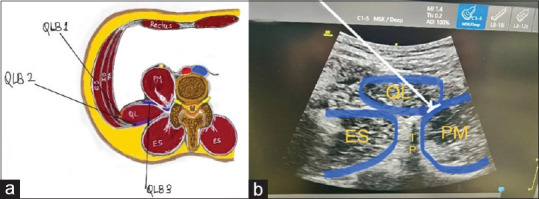

Material and methods: In this randomized, open-label, single-centered trial, 64 patients belonging to the American Society of Anesthesiologists, physical status grade I and II, 18-65 years of age, scheduled for laparoscopic nephrectomy were included. Patients were randomized into the QLB group and the control group. After surgery, the QLB group received transmuscular QLB with a 0.4 mL/kg bolus of 0.25% ropivacaine and catheter insertion for continuous infusion of 0.25% ropivacaine at 0.1 mL/kg/h. Patients in both groups received fentanyl (0.5 μg/kg) as rescue analgesia by IV PCA pump.